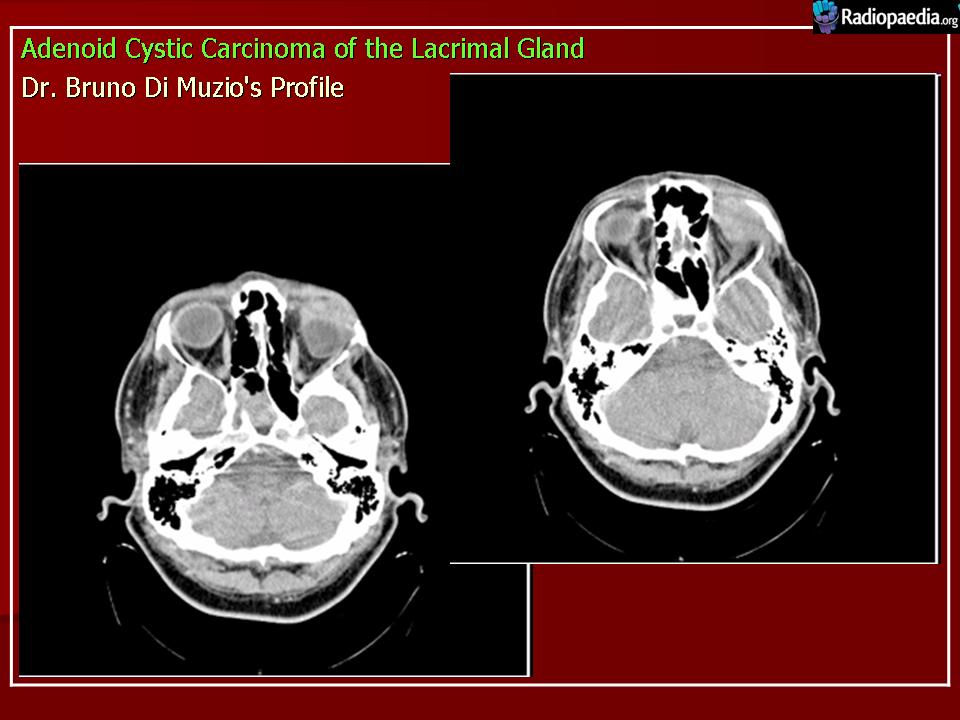

Диагноз устанавливают только после гистологического исследования. Предположительный диагноз может быть установлен на основании анализа клинических симптомов и результатов инструментального исследования. При рентгенографии на фоне увеличенной в размерах орбиты выявляются участки костной деструкции, чаще в верхненаружной, верхней и наружной стенках орбиты. Компьютерная томография позволяет определить протяженность тени опухоли, неравномерность ее краев, распространение в прилежащие экстраокулярные мышцы и неравномерность контуров костной стенки орбиты или ее полное разрушение, а ультразвуковое исследование — лишь наличие тени опухоли и ее плотность. Радиосцинтиграмма орбиты при аденокарциноме характеризуется увеличением коэффициента асимметрии, свойственного злокачественным опухолям. Информативна дистанционная термография, особенно с сахарной нагрузкой. Уточнить диагноз помогает дооперационная тонкоигольная аспирационная биопсия.